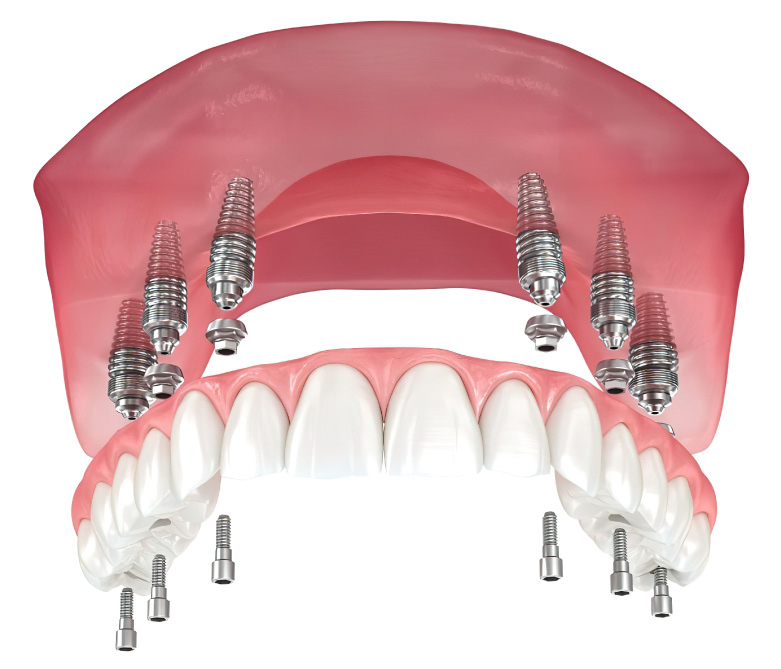

All-on-4 Implants

A technique that uses four implants to support a full arch of replacement teeth, ideal for patients with limited bone density.

All-on-6 Implants

Similar to All-on-4 but with six implants, providing enhanced stability for a full arch of replacement teeth.